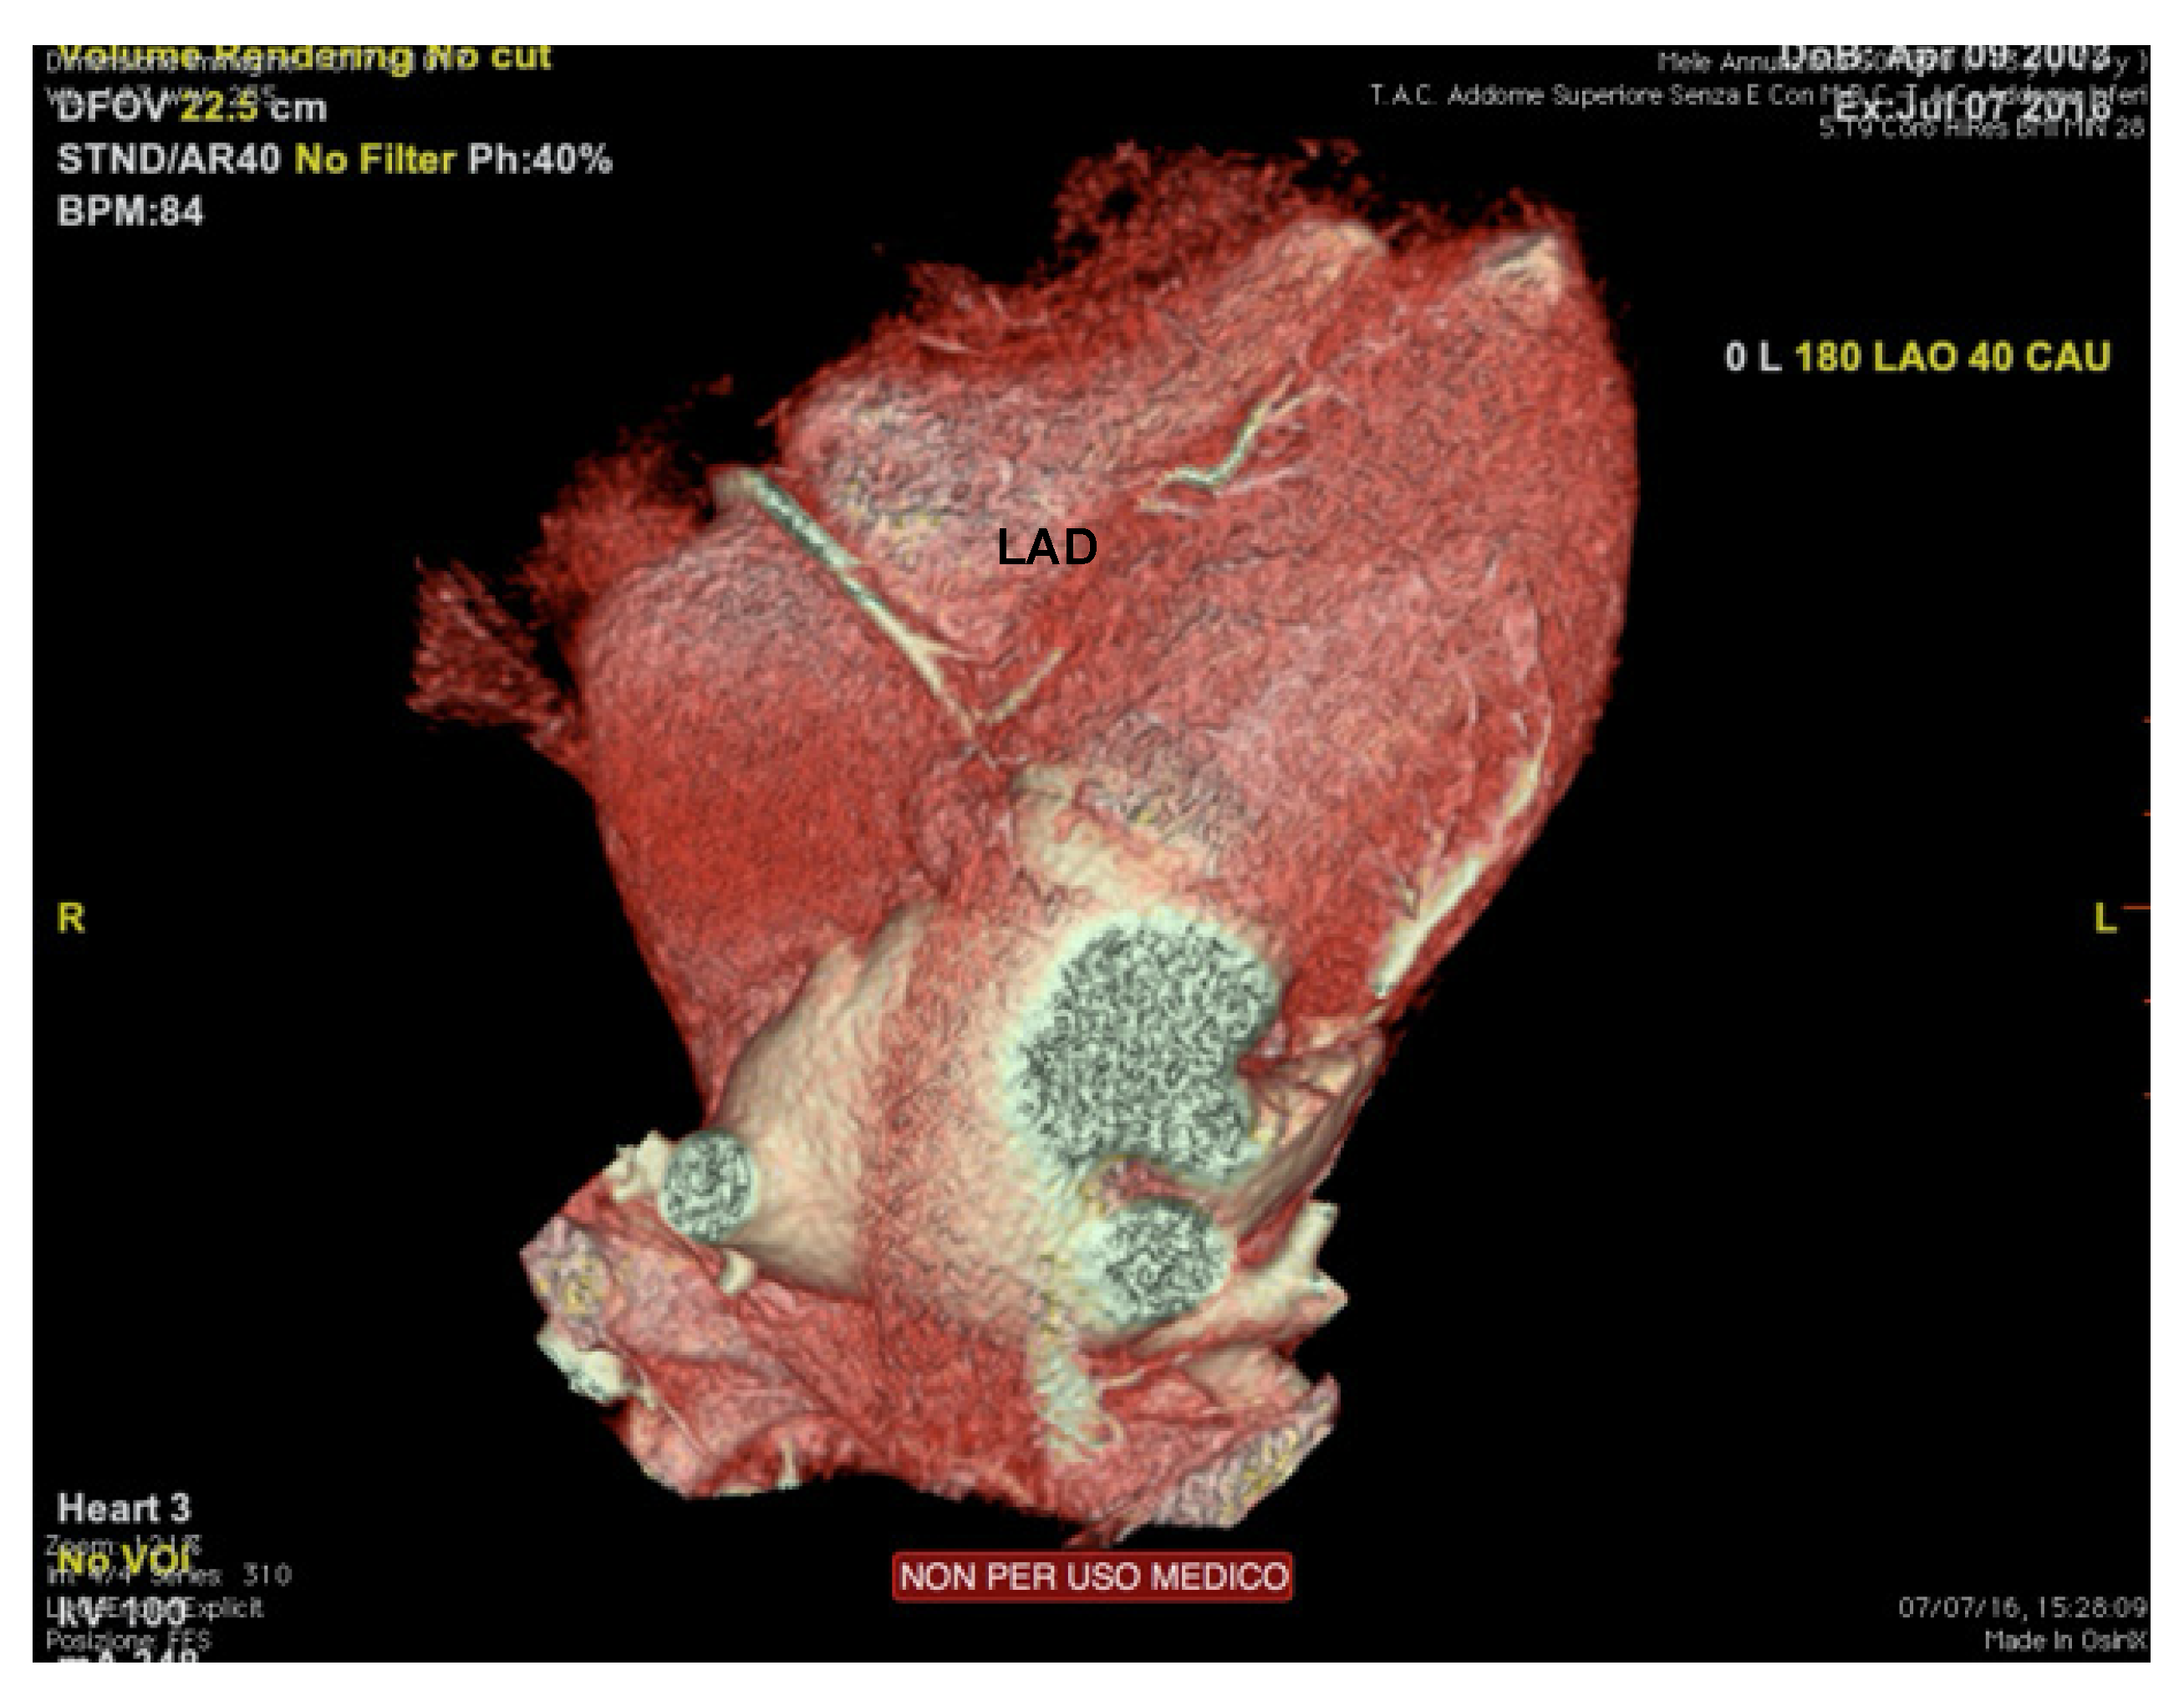

Cardiac computed tomography (CCT) shows high accuracy in the evaluation of coronary arteries’ origin, course (including intramural), and termination [1] (Figure 6). Therefore, the main indication to perform a coronary CT angiography (CTA) is the suspicion of coronary artery anomalies (generally under 35 years of age) or atherosclerotic coronary artery disease (over 35), raising from clinical markers (exertional syncope, angina, or arrhythmias), or abnormal exercise test [76].

Figure 6.

Cardiac computed tomography of an endurance athlete (runner) symptomatic for syncope. The figure shows an intramural course of the left anterior descending coronary artery. LAD: left anterior descending.

All athletes with indeterminate, suspected, or confirmed anomalous coronary artery anatomy following echocardiography should undergo CTA or CMR, according to institutional preferences and expertise.